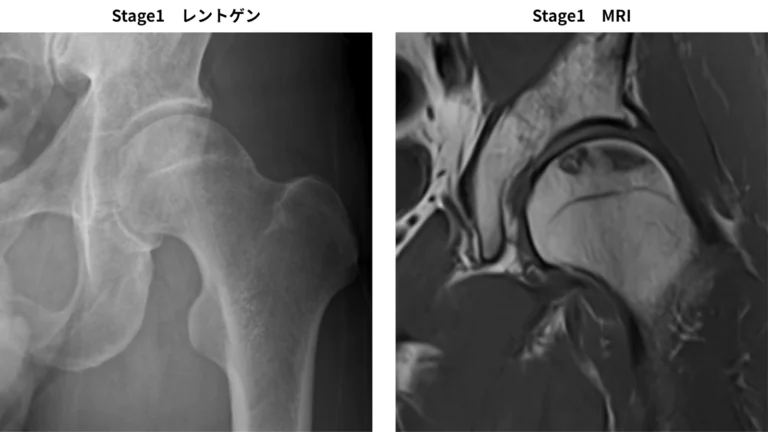

1. Stage 1:X線では異常なし、MRIやシンチグラムで異常あり。